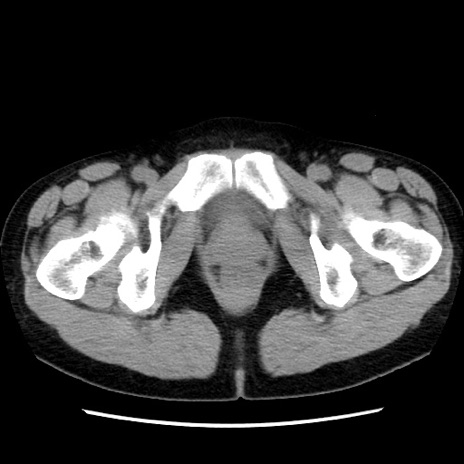

矢状断像

【症例】 50歳代女性

【主訴】 腹痛

【現病歴】前日生レバーを食べた。今朝に排便あり。 昼前に突然発症の腹痛を生じ、当院救急外来を受診した。

【既往歴】 子宮筋腫にてで子宮全摘後

【身体所見】 意識清明、腹部:平坦、軟、下腹部やや左を中心に圧痛・反跳痛あり、筋性防御あり

【データ】WBC 7800、CRP 0.07